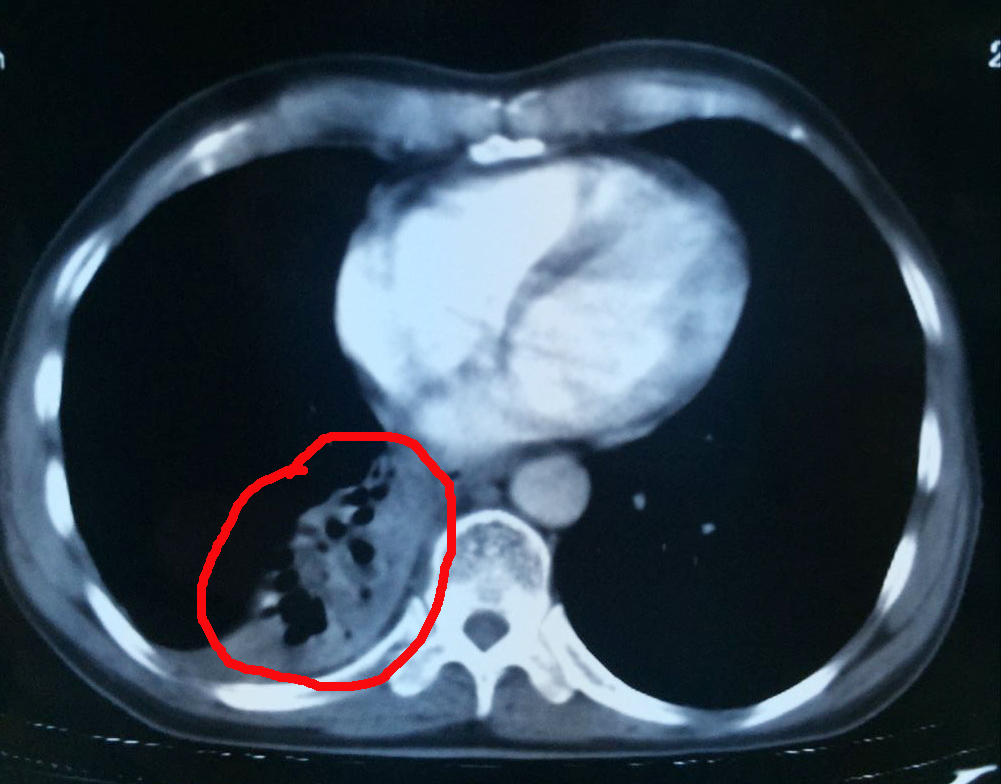

6月28日,楊清貴接受了介入治療,手術順利。術后楊清貴沒有明顯的不適癥狀,24小時后正常行走。為進一步殺滅腫瘤,楊清貴又接受了氬氦刀治療。據(jù)了解,氬氦刀適用于各種類型的實體瘤,其治療原理是在CT的引導下,將冷凍穿刺針插入腫瘤里,注入氬氣,使冷凍針尖迅速降溫至零下140-160攝氏度,將腫瘤冷凍成冰球,再注入氦氣使冷凍針尖迅速升溫至40攝氏度左右,如此反復兩到三個循環(huán),讓腫瘤細胞崩解凋零。

術前的楊清貴心情十分忐忑,但聽了醫(yī)生一番話后又恢復了平靜。“林菁醫(yī)生耐心地跟我們解釋了治療有哪些風險,如腫瘤靠近肺門以及氣管,冷凍治療可能會造成出血、咳血、氣胸等,但很快又給我們服下定心丸,‘醫(yī)院每天都做5-6臺這樣的手術,手術的專家經(jīng)驗都十分豐富,出現(xiàn)并發(fā)癥的情況極少。’”張英友說道。據(jù)了解,經(jīng)過近3個月的綜合治療,目前楊清貴的腫瘤幾乎全部消失,胃口、睡眠等恢復良好,身體與常人無異。

腫瘤治療中